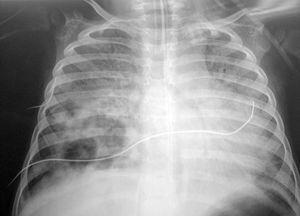

El paciente presentaba una coagulopatía que requirió tratamiento con plasma fresco congelado y vitamina K, así como anemia de 8 g/dl de hemoglobina (Hg) que requirió transfusión de concentrados de hematíes. La función respiratoria fue empeorando progresivamente, presentando presiones altas en la vía aérea (pico de 45-50 cm H2O, meseta de 19 cm H2O, compliance dinámica de 3,4 ml/cm de H2O y estática de 12 ml/cm H2O). Se asoció NO2 hasta 30 ppm al tratamiento. Tras aumentar progresivamente la presión positiva al final de la espiración (PEEP) hasta 7 cm H2O, el pulmón derecho aparecía más aireado, y tras la resolución del componente atelectásico que estaba asociado a la neumonía (fig. 1) se apreciaron dos imágenes compatibles con abscesos o bullas en el pulmón derecho (fig. 2). La evolución posterior fue hacia un síndrome de distrés respiratorio agudo (fig. 3). Se inició tratamiento con ventilación de alta frecuencia con una mejoría inicial de la oxigenación que no se mantuvo posteriormente.

Figura 3. Síndrome de distrés respiratorio agudo.